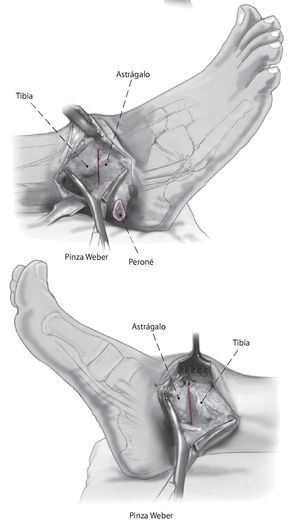

La técnica quirúrgica se ilustra en las figs. 1-13.

Fig. 8 Compruebe la alineación apretando a la vez los cortes del astrágalo y de la tibia. Debe cuidarse la alineación neutra del retropié para que la altura sea idéntica en todas las direcciones.

Fig. 9 Compruebe la alineación y aplique fijación provisionalmente con el uso de dos pinzas Weber grandes. Asegurarse de que el astrágalo esté colocado un poco posterior respecto al margen distal de la tibia anterior para reducir así el brazo de palanca anterior del pie.